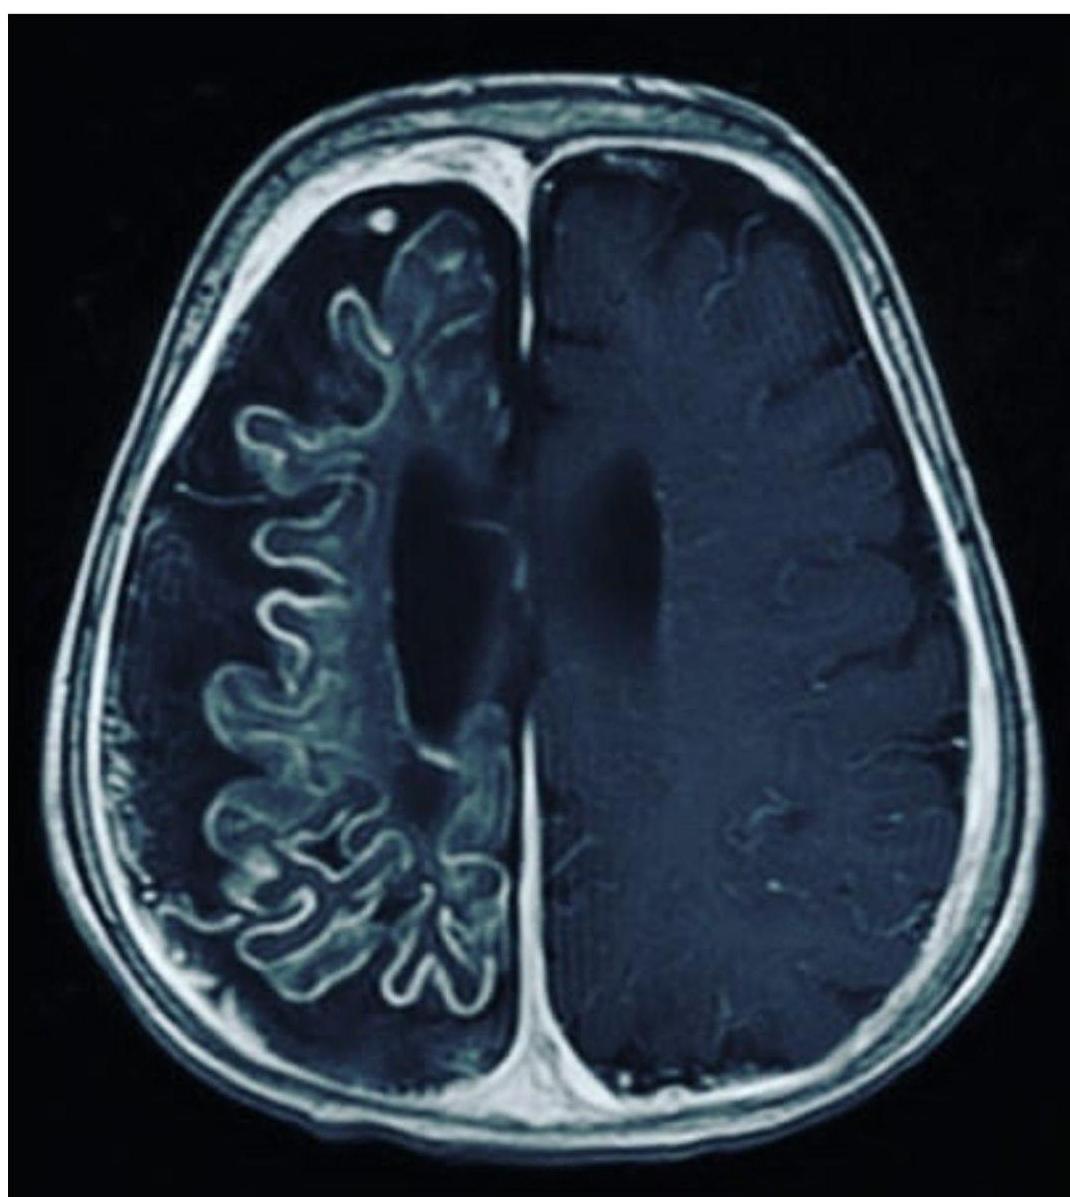

- Best Diagnostic Study: Brain MRI with gadolinium contrast (demonstrates leptomeningeal angioma).

- Leptomeningeal Angioma: Vascular anomaly of the leptomeninges on the ipsilateral side.

- Brain Atrophy & Calcification: Underlying brain becomes atrophic and calcified (“Tram track” calcification).